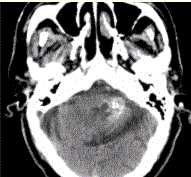

问题 男性,80岁,左耳听力下降伴头晕半年。头CT显示如下图。 可能的诊断为

选项 A.钙化灶 B.急性出血 C.动静脉畸形 D.海绵状血管瘤 E.胶质瘤 F.发育性静脉畸形 G.脑囊虫

答案 ABCDFG